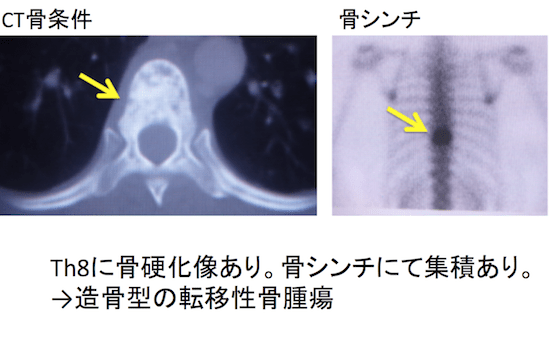

全身骨シンチグラフィ 乳癌 肺癌 前立腺癌等の骨転移病巣の検出

全身骨シンチグラフィ 乳癌 肺癌 前立腺癌等の骨転移病巣の検出

骨シンチグラフィによる骨転移の診断 Bone Scan Ct Mri画像診断